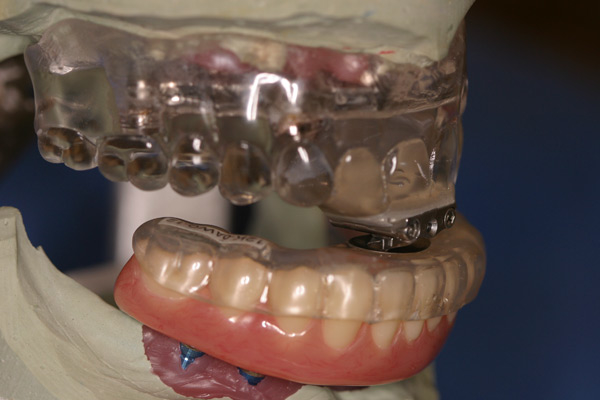

Problem: This patient had a series of problems that resulted with tooth loss. He also has a problem with sleep apnea. He wanted something fixed and stable.

Plan: Our plan… placed four implants on the lower with a fixed/hybrid prosthesis. Placed five on the upper arch with a titanium bar and snap attachments to allow a special one of the kind sleep apnea device.

He really likes his new smile and he gets a great nights rest as well.